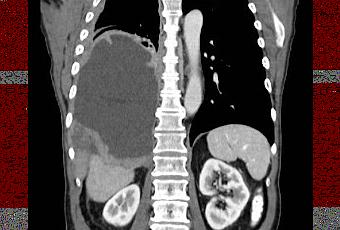

Mésothéliome malin dans le poumon droit - à gauche sur cette image -, vu par tomodensitométrie en coupe coronale.

Source iconographique et légendaire: https://fr.wikipedia.org/wiki/M%C3%A9soth%C3%A9liome